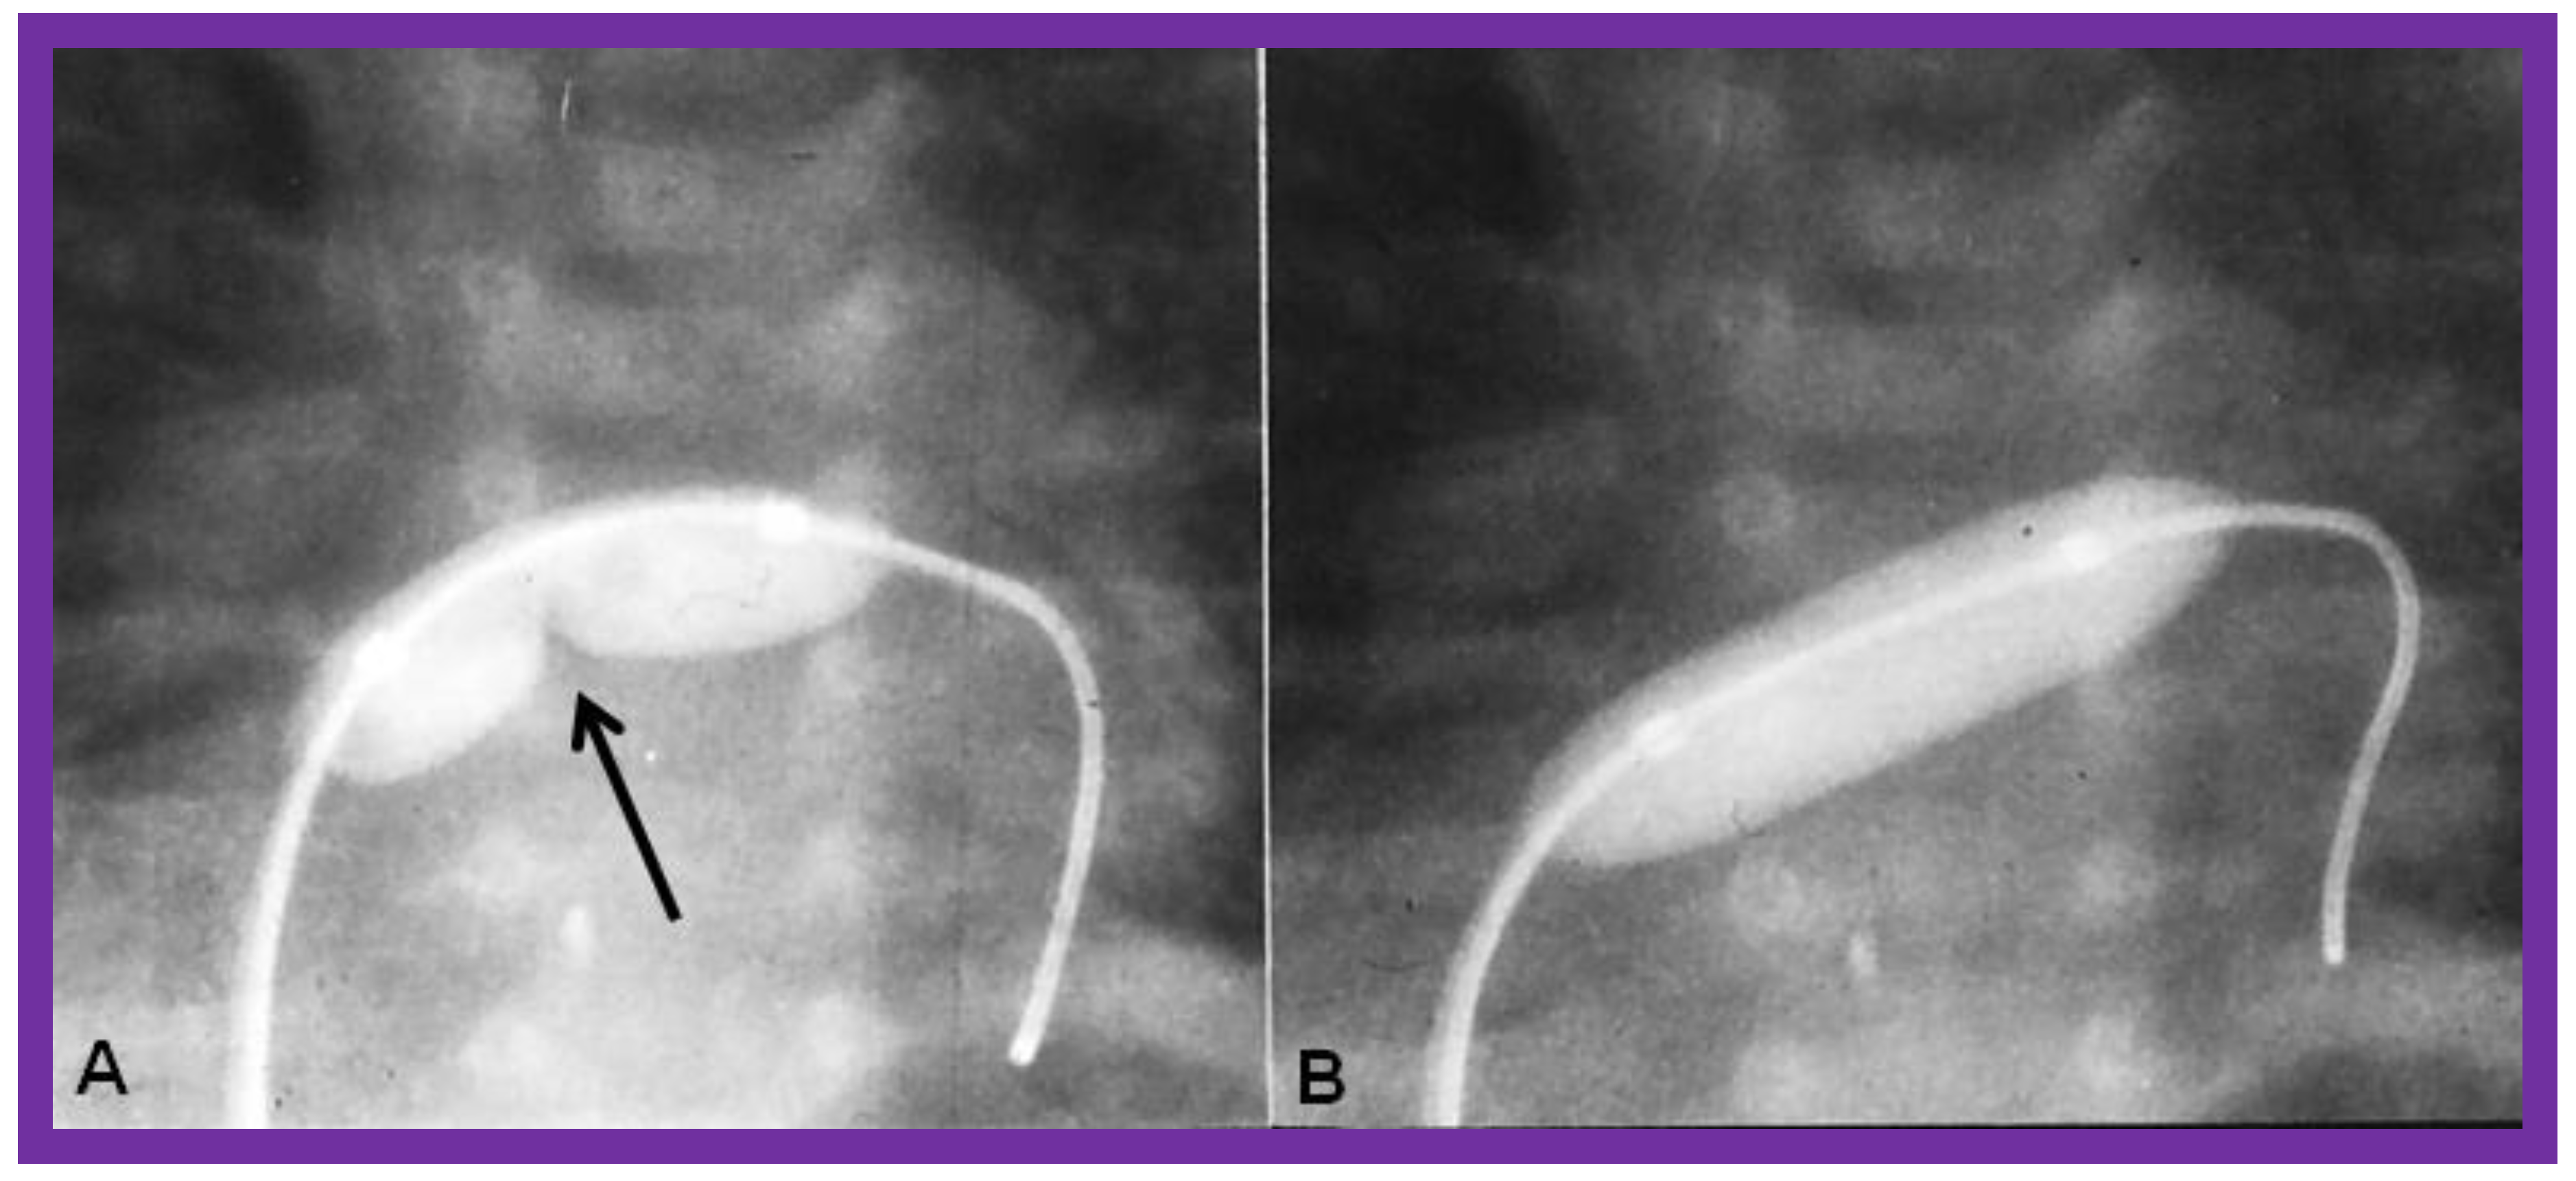

9. Cardiac Catheterization with Angiography, Magnetic Resonance Imaging (MRI) and Computed Tomography (CT)